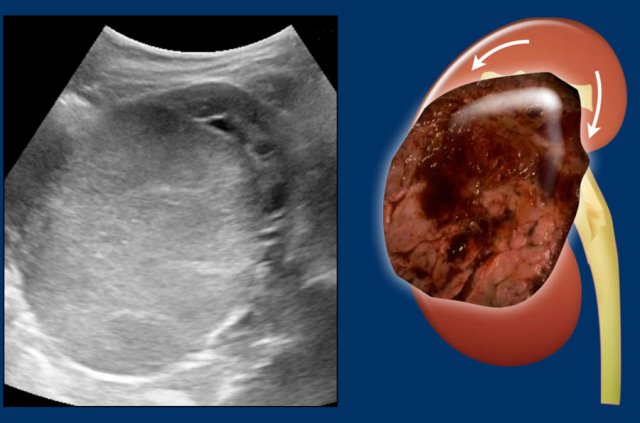

Left sided Wilms' tumor in a one-year-old girl.

The remnant of the kidney is draped over the tumor, the “claw sign”.